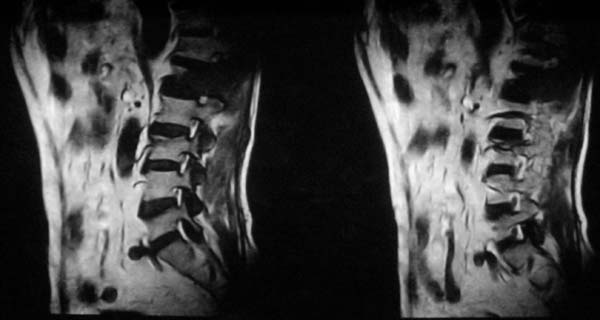

病史特点:

1.中年男性

2.腰疼,双下肢麻木1月。

3.ct 可右肾上腺占位,腰1椎体及附件可见骨质破坏及软组织肿块。

4.mri:腰1椎体及附件t1wi低信号,t2wi高信号。

考虑右侧肾上腺癌骨转移.或右肾上腺及骨均为转移瘤。